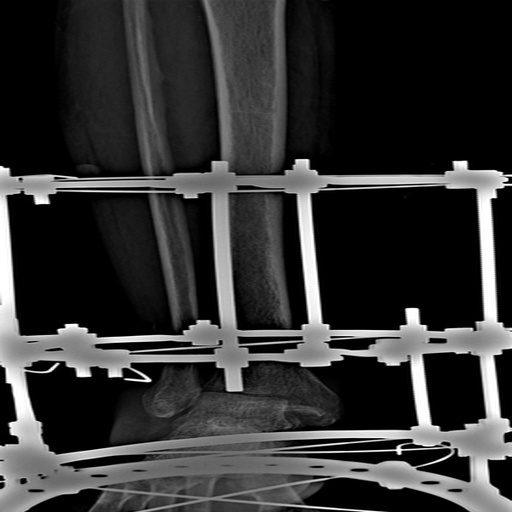

It identifies hairline fractures in medical imaging